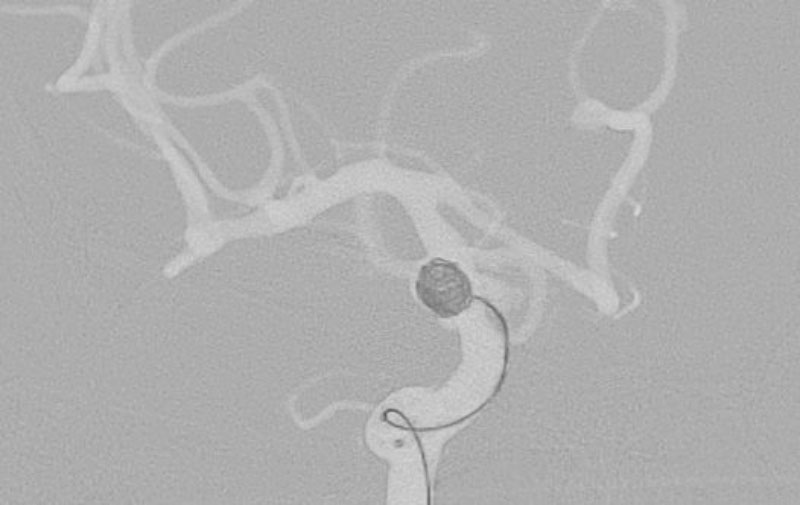

'25年11月

くも膜下出血

右内頚動脈後交通動脈

分岐部動脈瘤破裂

60代

救急外来

No.1593 手術前

No.1593 手術中

No.1593 手術後